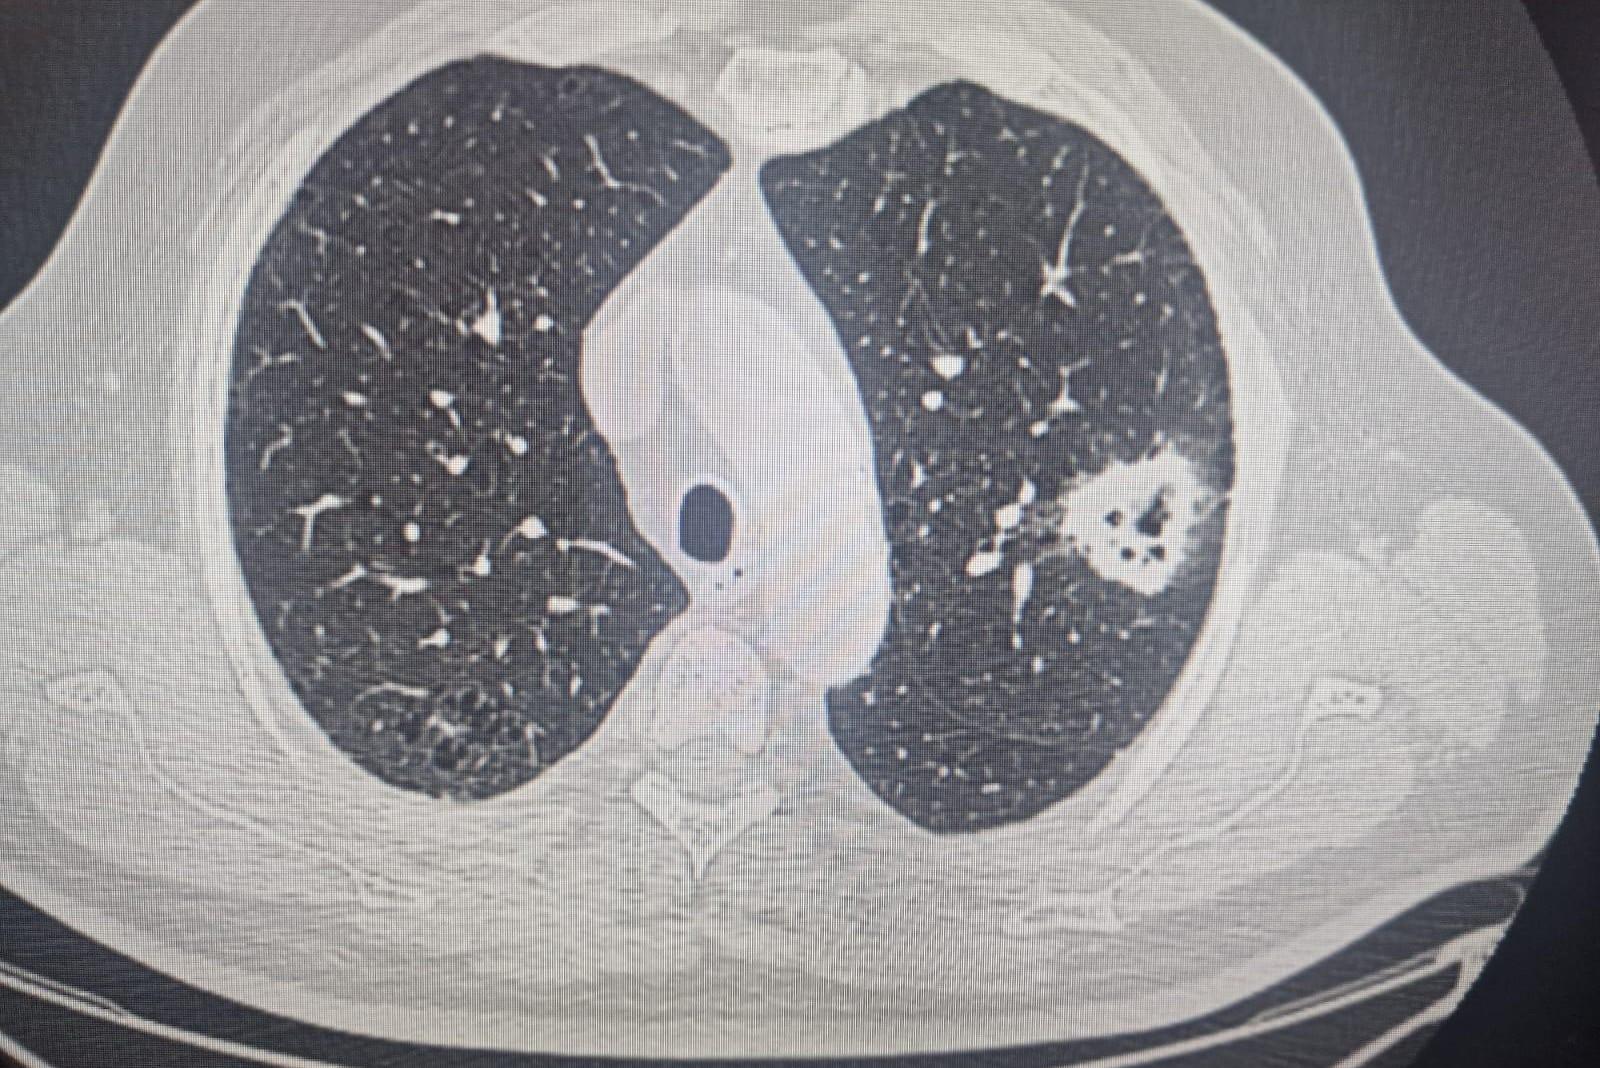

«Резко стал слух пропадать»: как пациент случайно узнал о раке легких и чему учит его опытДесять лет 75-летний Михаил Пигурнов живет в ремиссии, узнали его историю

6 сентября, 2025, 19:00

«Клетки мутируют у всех»: врач — об одном из самых коварных раков, от которого гибнут миллионыДве трети всех раков легкого находят у мужчин

6 августа, 2025, 15:00